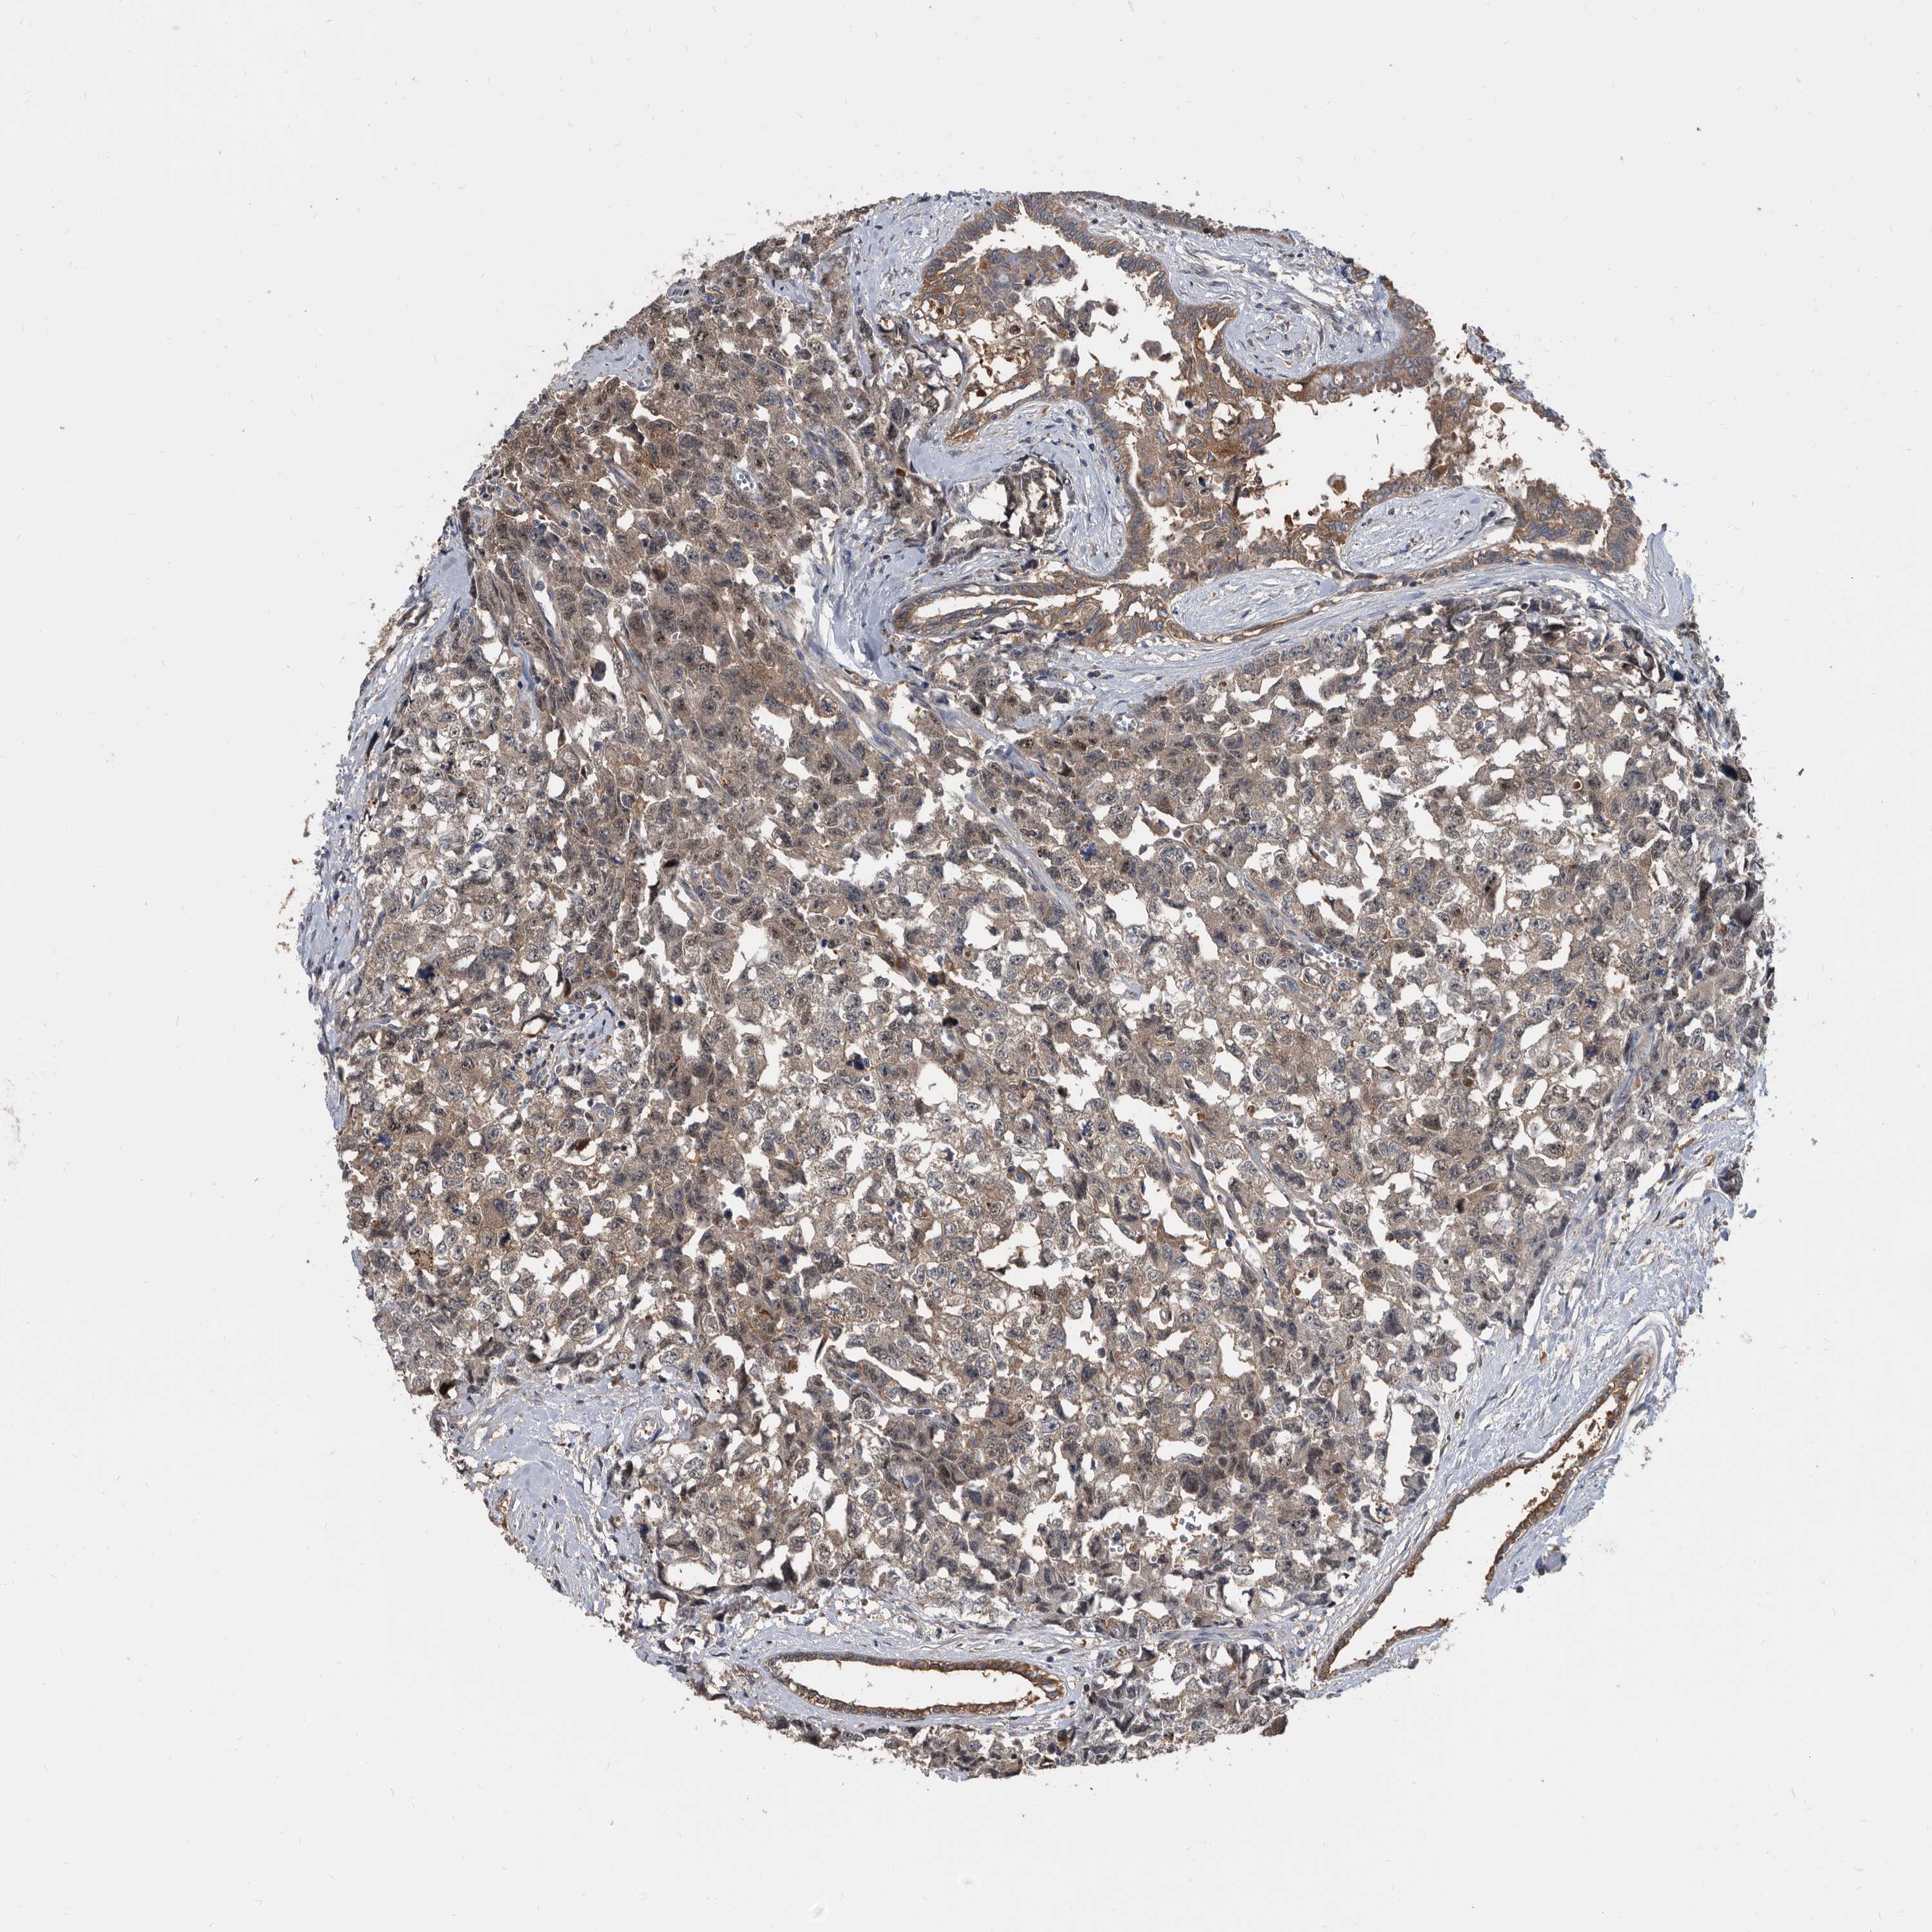

TESTIS CANCER - Protein expressioni

A mouse-over function shows sample information and annotation data. Click on an image to view it in a full screen mode. Samples can be filtered based on level of antibody staining by selecting one or several of the following categories: high, medium, low and not detected. The assay and annotation is described here.

Note that samples used for immunohistochemistry by the Human Protein Atlas do not correspond to samples in the TCGA dataset.

Antibody stainingi

Antibody staining in the annotated cell types in the current human tissue is reported as not detected, low, medium, or high, based on conventional immunohistochemistry profiling in selected tissues. This score is based on the combination of the staining intensity and fraction of stained cells.

Each image is clickable and will lead to virtual microscopy that enables deeper exploration of all samples and also displays staining intensity scores, fraction scores and subcellular localization as well as patient and tissue information for each sample.

Antibody HPA029700

Antibody HPA029701

Antibody HPA029702

Antibody HPA029703

Carcinoma, Embryonal, NOS

Seminoma, NOS